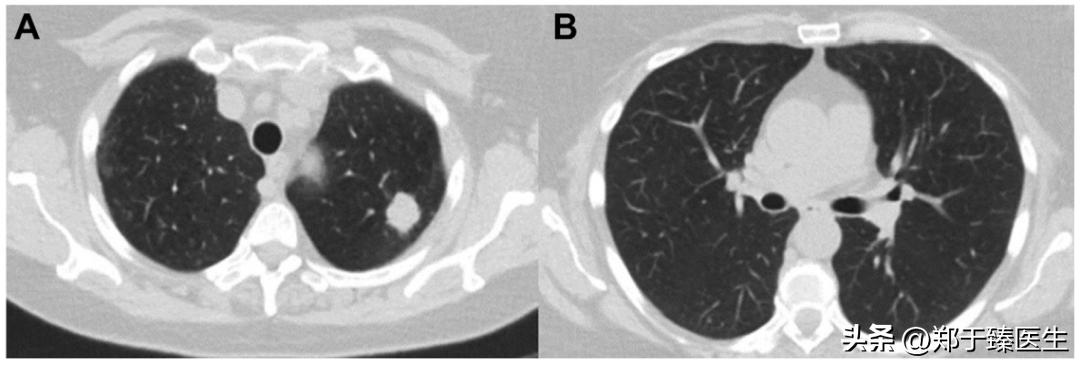

2022年,<Ann Thorac Surg>期刊刊载了一篇个案报道,详细展现了真实世界中关于手术决策的具体权衡。

这是一名中年女性患者,2021年1月初诊时发现左上肺2cm实性病变,符合肺癌特征。

但在术前检查时发现该患者感染了新冠病毒,因此,其手术被暂停。

此后,患者一度出现胸闷气促不适,但在社区医院的处理下逐渐好转,并在感染新冠病毒以后第6周复测核酸转阴。

此时重拍胸部CT,发现左上肺实性病灶较前增大,双肺仍有多发炎症表现。

最终在充分权衡手术利弊的情况下,为患者开展了微创条件下的亚肺叶手术,切除了左上肺的固有段,术后患者恢复顺利而出院。

从目前的研究结果来看,针对一个大于2cm的实性病灶,其标准治疗方案毋庸置疑,仍然是肺叶切除。

而这个病人左上肺的实性结节>2cm,最终只做了固有段切除,其背后更多地是对新冠病毒感染导致肺炎的妥协。